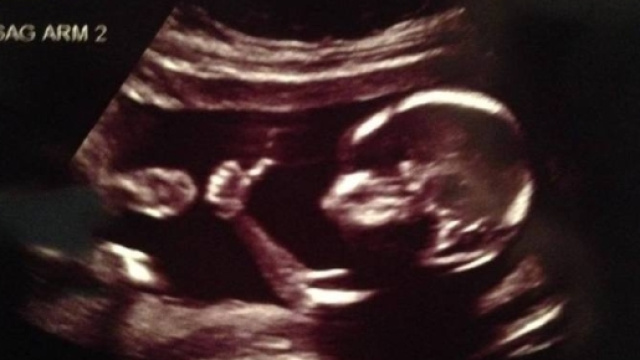

Se un medico, durante un monitoraggio, scopre un'anomalia del feto può mentire alla donna incinta? In Texas sì. Nelle ultime ore, nello Stato americano è stato approvato dal Senato un discusso disegno di legge che autorizza i medici a dire il falso alle donne incinte. Molti attivisti sono già sul piede di guerra e sottolineano che si vuole, ancora una volta, impedire alle donne di esercitare il diritto all'aborto, tra l'altro garantito dalla Costituzione. In base al suddetto disegno di legge i medici del Texas e il servizio sanitario nazionale non potranno essere denunciati dai genitori di bimbi disabili.

Se un medico texano, in futuro, ravviserà delle malformazioni del feto ma non lo comunicherà ai genitori non potrà essere denunciato. Lo prevede un disegno di legge, approvato nelle ultime ore in Senato, che dovrà superare il vaglio della Texas House of Rapresentatives. I promotori del disegno di legge hanno detto che la nuova normativa eviterà altre interruzioni di gravidanza e tutelerà i medici, che così non dovranno affrontare lunghi e inutili processi. Si vuole, in sostanza, difendere i bimbi con disabilità. Brandon Creighton, senatore repubblicano che sostiene il disegno di legge, reputa assurdo condannare i medici che si schierano dalla parte della sacralità della vita.